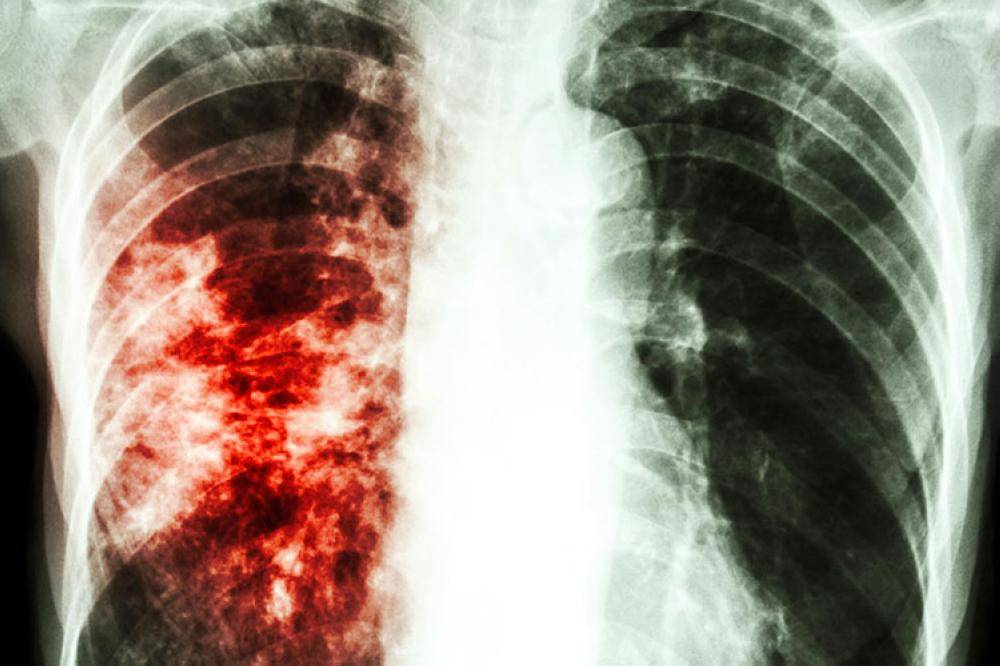

Фотографии бактерий, вызывающих бактериальные пневмонии у животных

Раздел: Другие животные